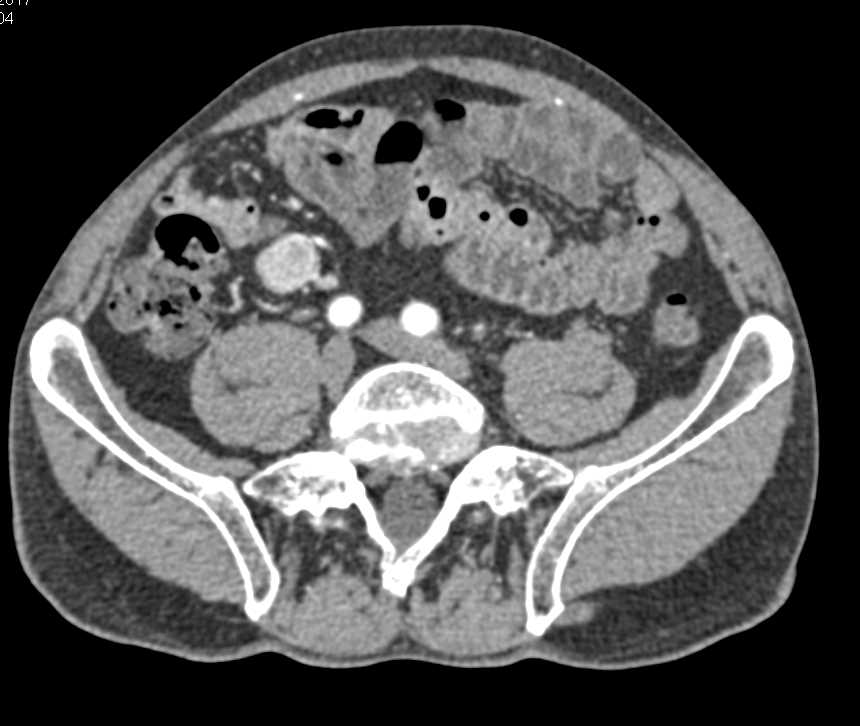

Small Bowel Carcinoid Tumor